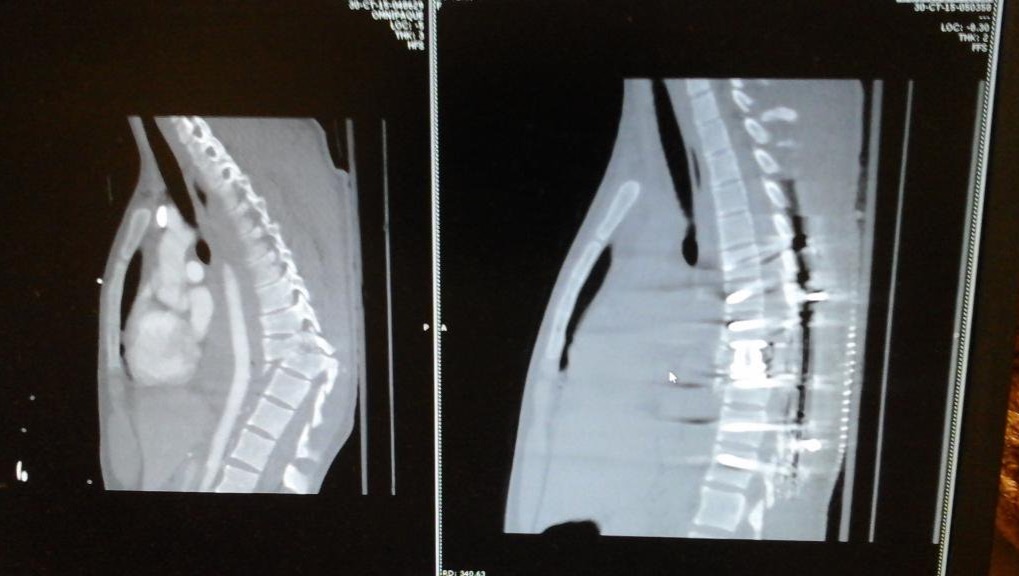

Lauren suffered a T-9 complete spinal cord injury from a car accident in 2015. This life changing injury is followed by a long journey of physical therapy to relearn how to walk and to keep the body healthy. The intense physical therapy required for SCI’s is unfortunately not covered by insurance so it is hard to continue consistently without assistance. Any amount helps and is appreciated <3 thank you for following on this journey